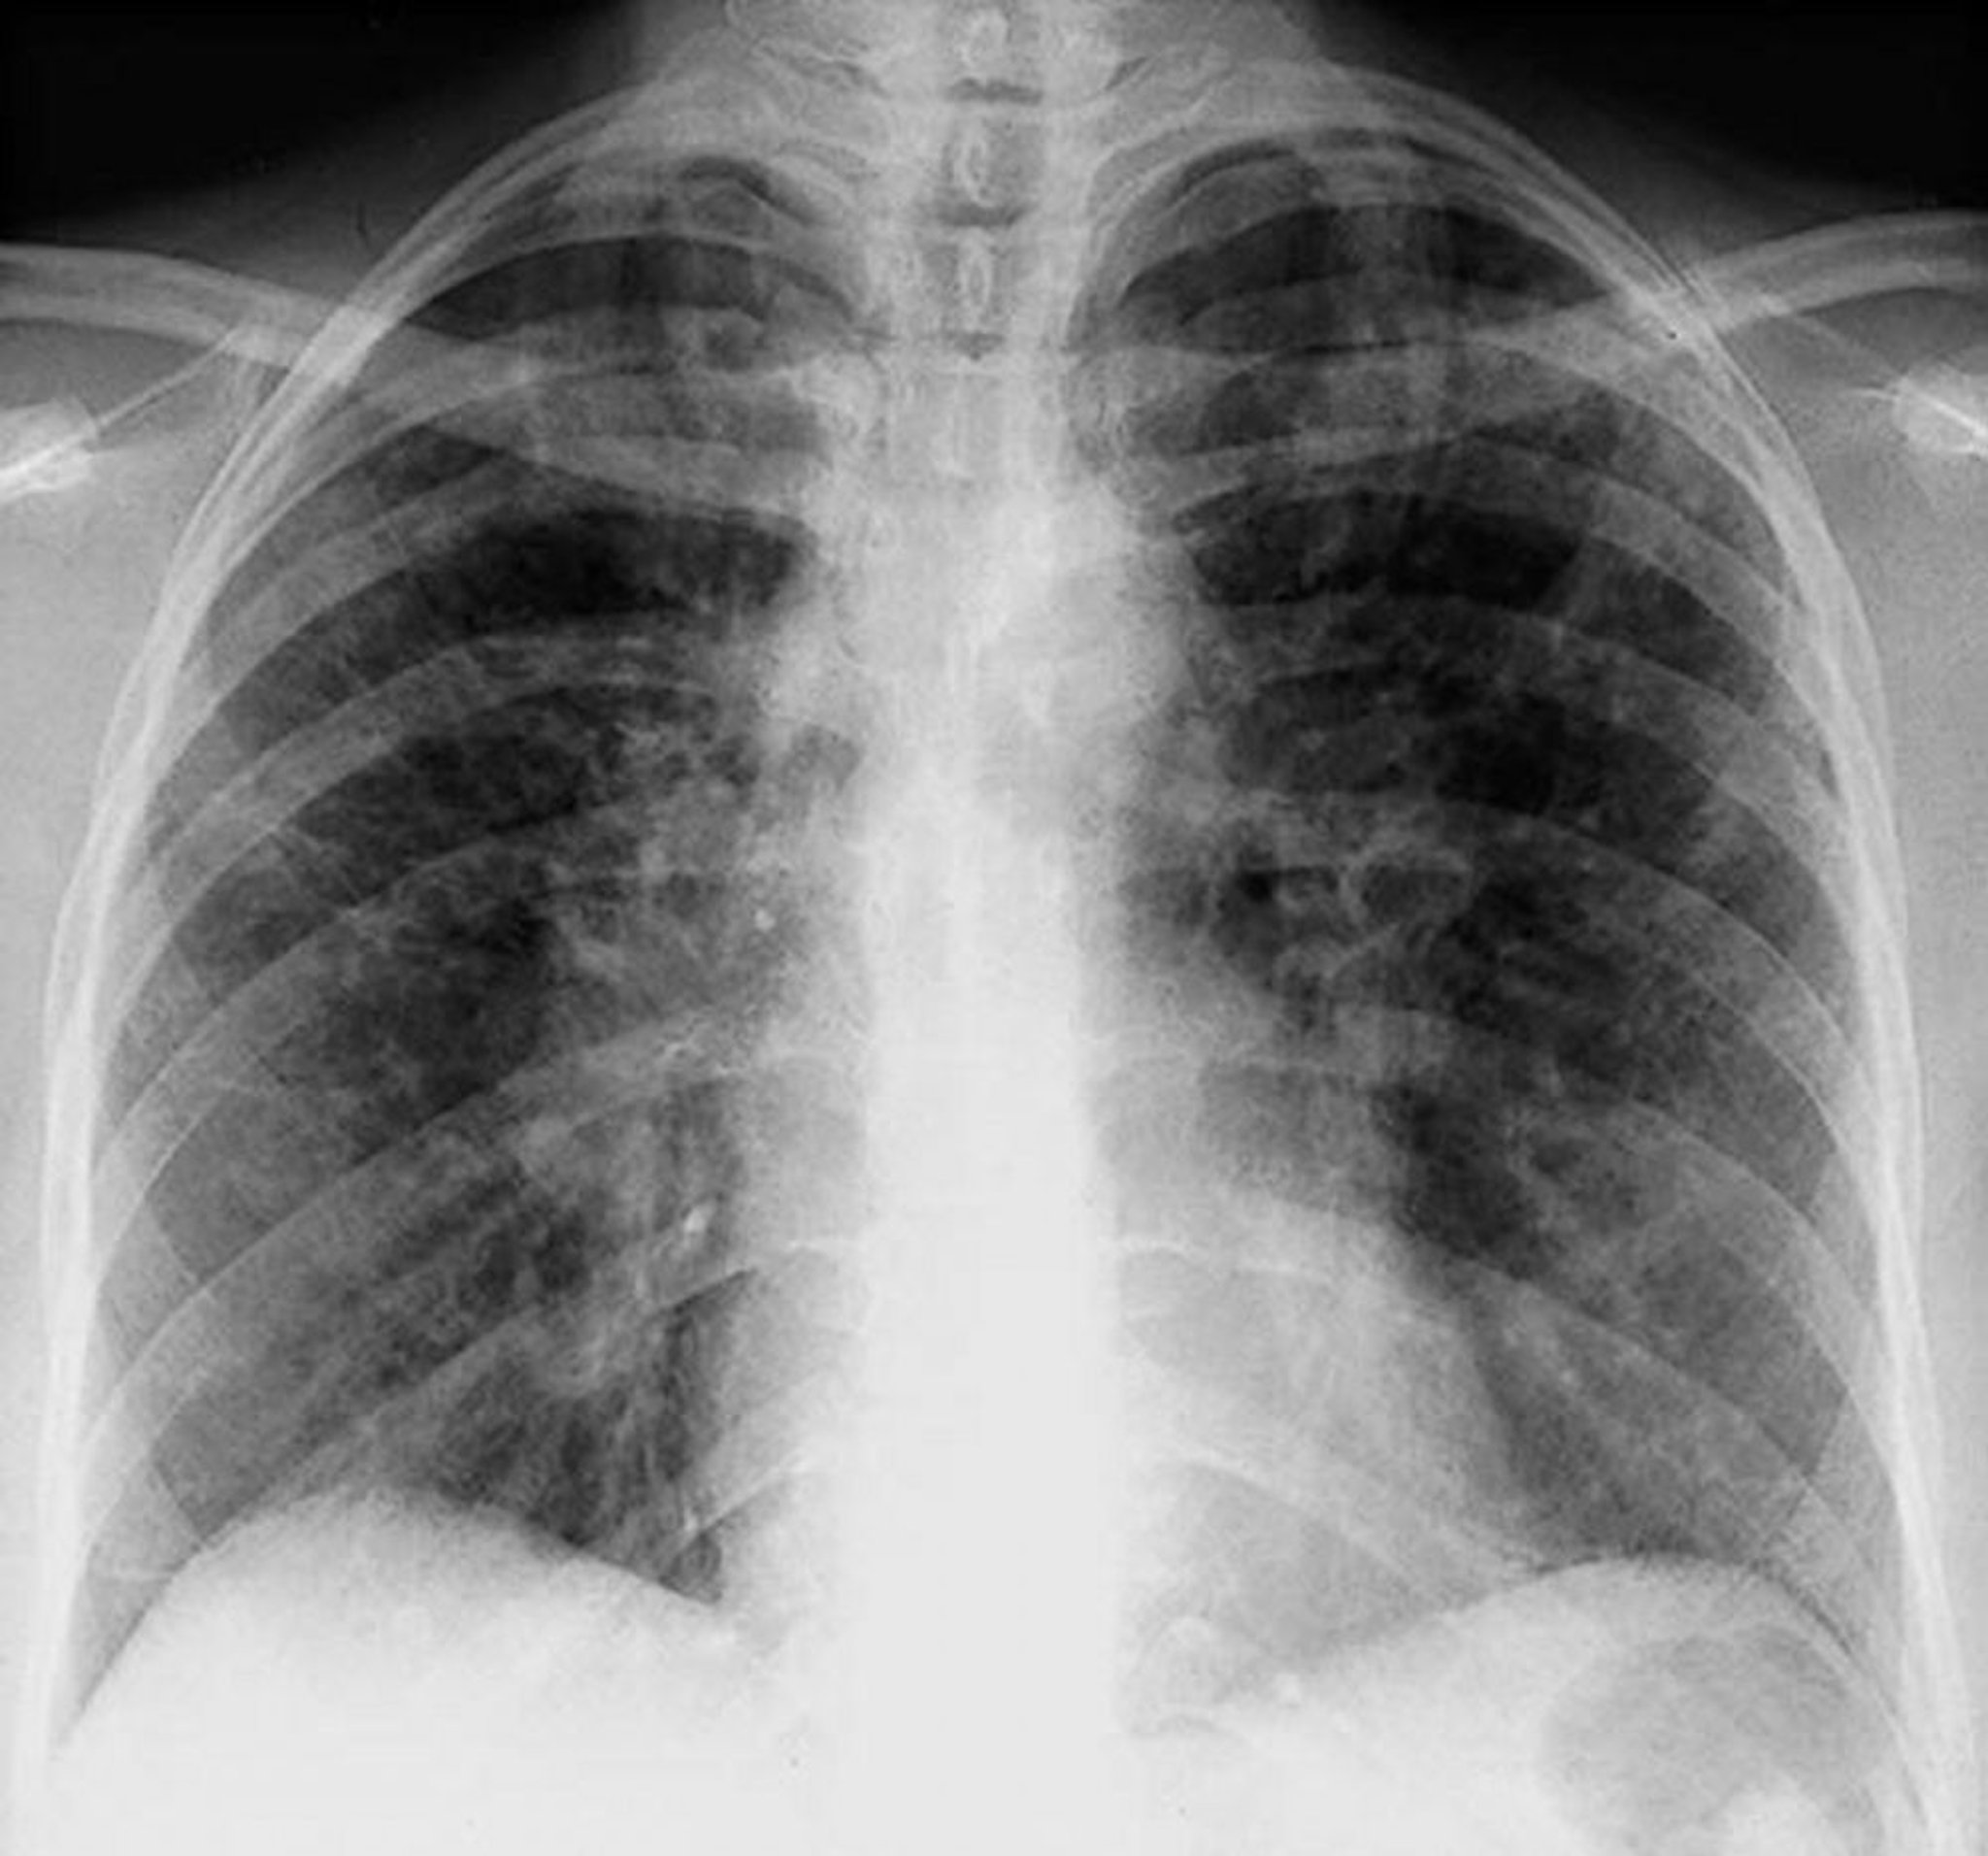

Sarkoidose (Stadium II)

Bilaterale hiläre Adenopathie mit interstitiellen Trübungen bei Sarkoidose im Stadium II.

By permission of the publisher. Aus Tanoue L, Elias J. In Bone's Atlas of Pulmonary and Critical Care Medicine. Edited by J Crapo. Philadelphia, Current Medicine, 2005.